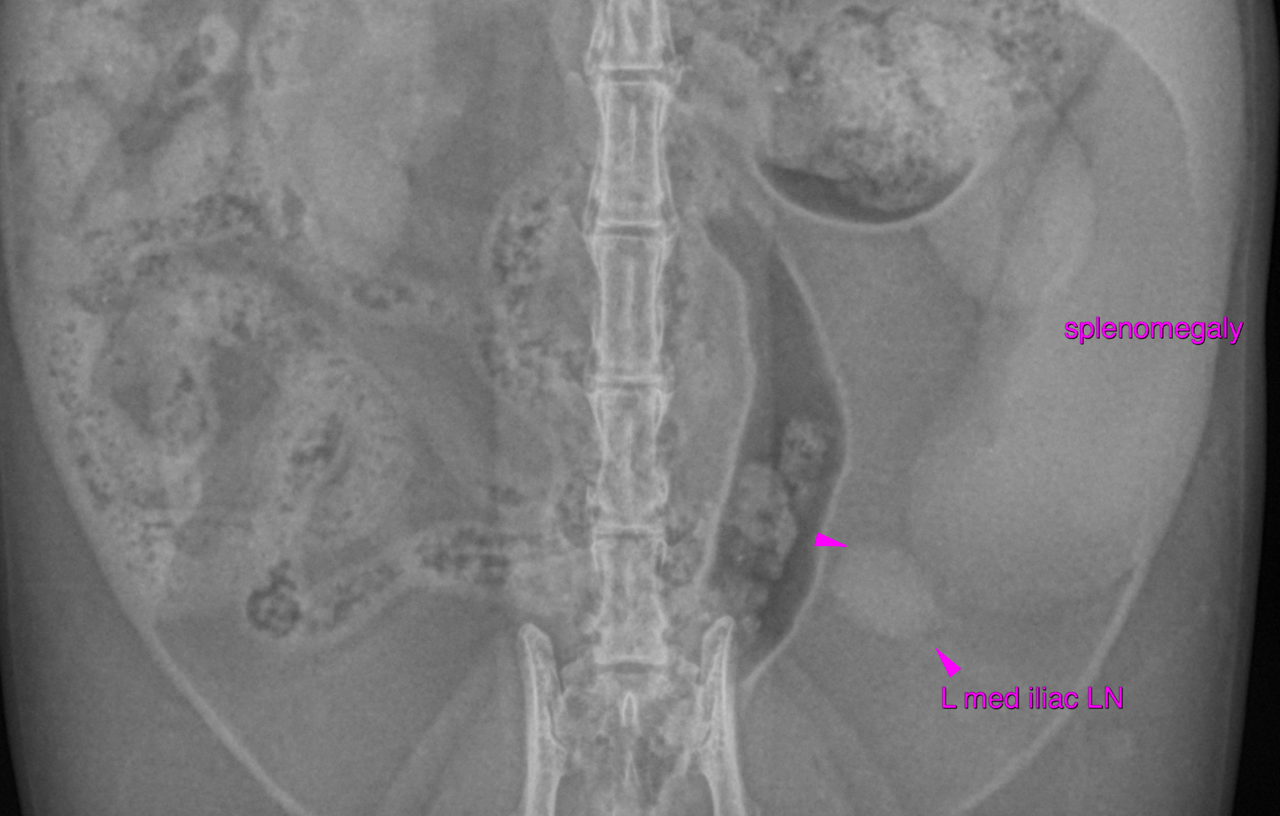

mediastinal fat. There is moderate generalized splenomegaly with rounded margins. The splenic head

is obscured on the lateral view, which is likely owing to the mass effect.

lymphadenomegaly or cyst as well. The left medial iliac lymph node reveals moderate enlargement and rounding.

The findings are suggestive for a multifocal neoplastic infiltrate involving the spleen

and lymph nodes. The bronchitis may be infectious (bacterial, viral, parasitic) or allergic in origin.